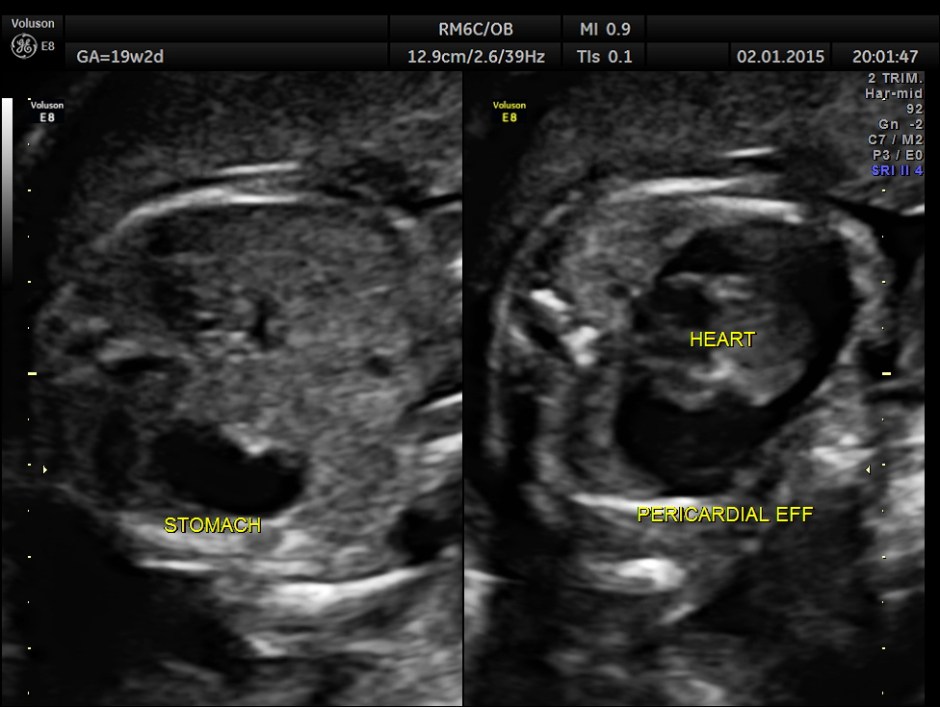

A 20 year old lady , 2nd gravida with one live normal child and history of consanguinity was referred for 2nd opinion for suspected cardiac anomaly.

A large pericardial effusion is seen.

This fetus had a large pericardial effusion with structural defect of the heart – VSD and disproportionately smaller left heart – possibly co-arctation of aorta . The patient was advised chromosomal studies and was lost for follow up.